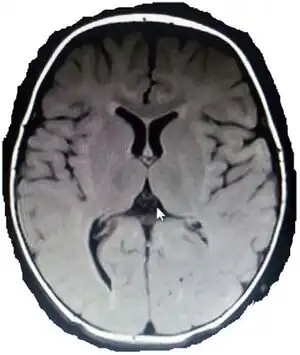

| MRI of infant born at term with spastic diplegia shows deep right occipital horn posteriorly with temporal/frontal minimal increment in CSF spaces | |